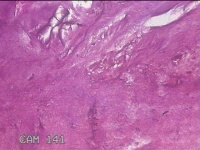

右侧中指指间关节背侧包块

性别

男

年龄

46岁

临床诊断

皮下结节

一般病史

发现右侧中指指间关节背侧一包块,伴间断性疼痛不适,考虑痛风结节。

标本名称

大体所见

灰白粉红色包块0.8x0.7x0.3cm一堆。

图2